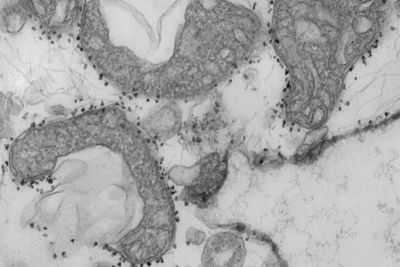

The results could explain why older adults, people with diabetes or heart disease have severe responses to COVID-19